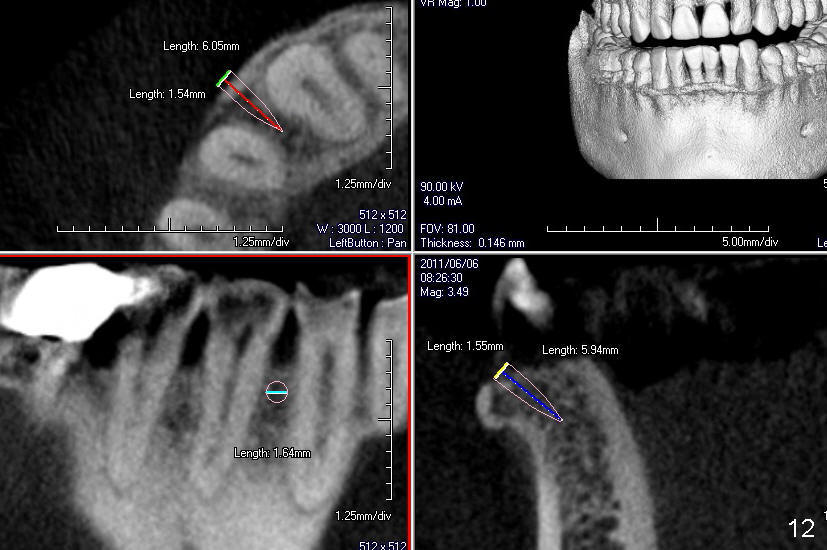

A male patient had trauma to the tooth #6 at the age of 13.  The affected tooth has remained asymptomatic for more than 30 years (Fig.1).   X-ray reveals an oblique root fracture (Fig.2 >) with radiolucency in the mesial alveolus (*, apparently normal trabecular pattern).  Six years later (Feb. 2011), an acute infection develops (Fig.4 *).  It requires incision & draining and antibiotic.  At that time, the trabecular pattern disappears around the fracture line mesially (Fig.3 *).  Four months later cone beam CT shows bone loss between #6 and 7 (Fig.5 *).  Root canal therapy is done as a palliative measure (Fig.6 R; C: Cavit).  Three months later, MTA (mineral trioxide aggregate) is placed in the coronal canal next to the fracture line (Fig.7 M).  It is hoped that MTA can promote nearby bone and cementum to regenerate to seal the fracture line.  Four months after MTA application, there is no sign of bone regeneration (Fig.8).  Bone is lost for approximately 7 mm.

Treatment plan is to extrude #6 by placing a mini-implant between #27 and 28 (Fig.11-13) until the fracture line is exposed and the chronic infection is controlled.  The most importantly, the extrusion is expected to bring down the mesial papilla and the alveolar bone.  If the remaining root is not stable, the tooth is extracted and replaced by an implant.